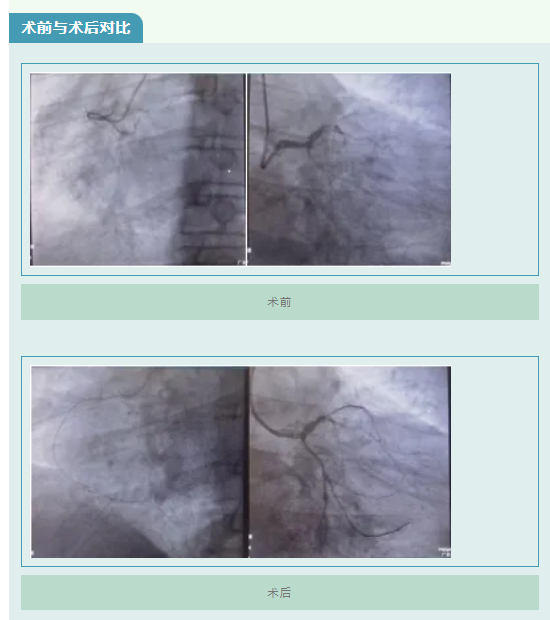

术前与术后对比

李先生的病情得到了显著改善,从术前的严重狭窄和闭塞,到术后的血流恢复。

在广东医科大学附属医院,李先生接受了冠脉造影,结果显示左优势型,右冠开口近段慢性闭塞性病变(CTO)并伴有钙化,前降支及回旋支全程弥漫严重狭窄并钙化,血流TIMI2级。诊断为高危复杂冠脉病变(CHIP),手术风险和难度较大。在与患者及家属充分沟通后,冠心病专科团队制定了一次性完全血运重建的手术策略。经过三个半小时的精细手术,运用了多种先进技术,包括实时融合平行导丝技术、超高压球囊扩张技术、药物球囊成形术和支架植入术,手术取得成功,患者症状得到显著缓解,并在7天后康复出院。